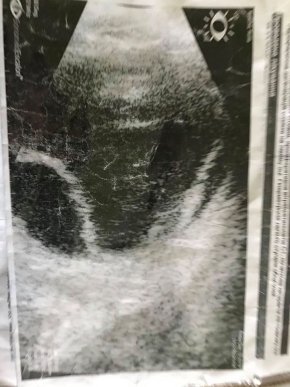

Наприкінці грудня 2019 року у вчительки молодших класів із Берегова Раїси Анатолівни Кушиль виявили важку недугу очей. У Києві, в Центрі медичної офтальмології, у жінки діагностували відшарування сітківки правого ока. Також була необхідна операція на заміну кришталика. Того ж місяця закарпатці провели первинну операцію 3 ступеня складності, яка вартувала родині 67 тисяч гривень.

"Наразі терміново необхідна повторна операція на праве око (мають видалити селікон і якщо сітківка прилягає добре, має відбутися закачка газу) та лазерна операція на ліве око. Вартість повторного лікування та оперативного втручання складає 70 тисяч гривень. І тому ми просимо всіх небайдужих людей допомогти хто чим зможе, бо ця сума є непідйомною для сім’ї Раїси Анатоліївни", – зазначає Оксана Бондарс.